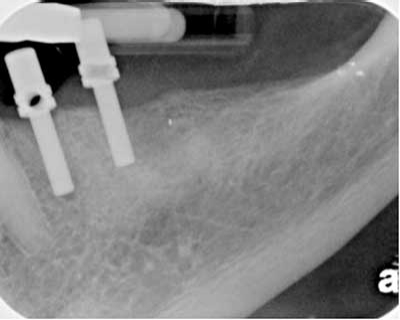

Fig. 3a

Fig. 3bFigs. 3a-3b: Lower second molar that upon access was referred because the mesial root was non-negotiable. Subsequent treatment gained patency of the mesial root and the root canal was performed with the Twisted File* and RealSeal* bonded obturation. Several clinical cases have been presented which highlight the value of a preoperative assessment of the case difficulty and reinforce the importance of early referral where needed. Emphasis has been placed on treating the patient and the tooth in the optimal manner that stresses an excellent final result over speed and profitability. The clinical value of patency and creation of the correct taper throughout the length of the root has been discussed to avoid unnecessary removal of tooth structure which would otherwise risk perforation, canal blockage, file fracture, and possible vertical root fracture. I welcome your feedback.*(SybronEndo, Orange, Calif., USA).